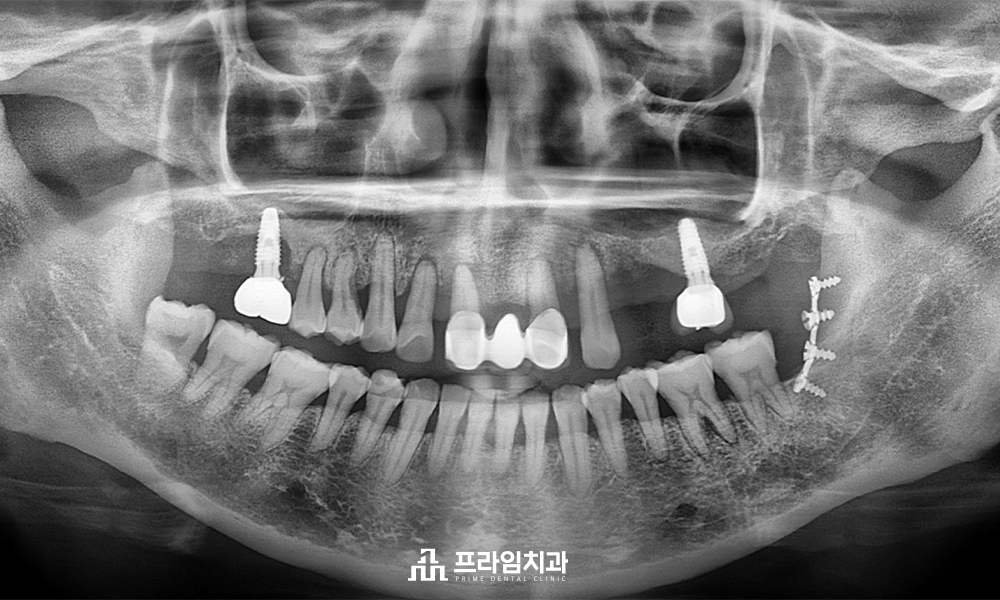

오늘은 예후가 좋지 않은

위쪽 자연치들을 발치한 후

전체 임플란트 식립을 진행하신

환.자분을 소개해 드리려고 합니다.

환.자분께서는 위쪽 치아가 흔들리고

통증이 느껴지신다며 내원해 주셨는데요.

남아있는 자연치들이 심한 치주염으로 인해

잇몸뼈가 녹아 장기적인 예후가 불량하다고

판단되어 발치 후 임플란트 수복을

계획하였습니다.